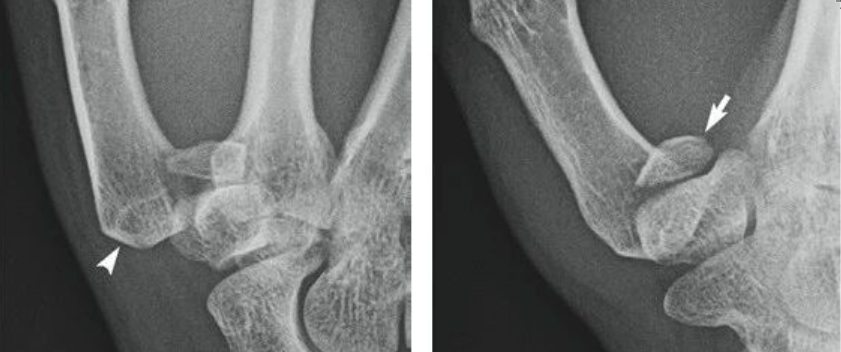

图1. 供区位置。(A) 鱼际皮瓣位置错误。此处离第一指蹼间隙和拇指基部太近,会对拇指的神经血管束构成威胁。(B) 皮瓣的正确位置应更靠近近端,位于鱼际区域上方。这个位置可防止拇指和第一指蹼间隙出现瘢痕挛缩。